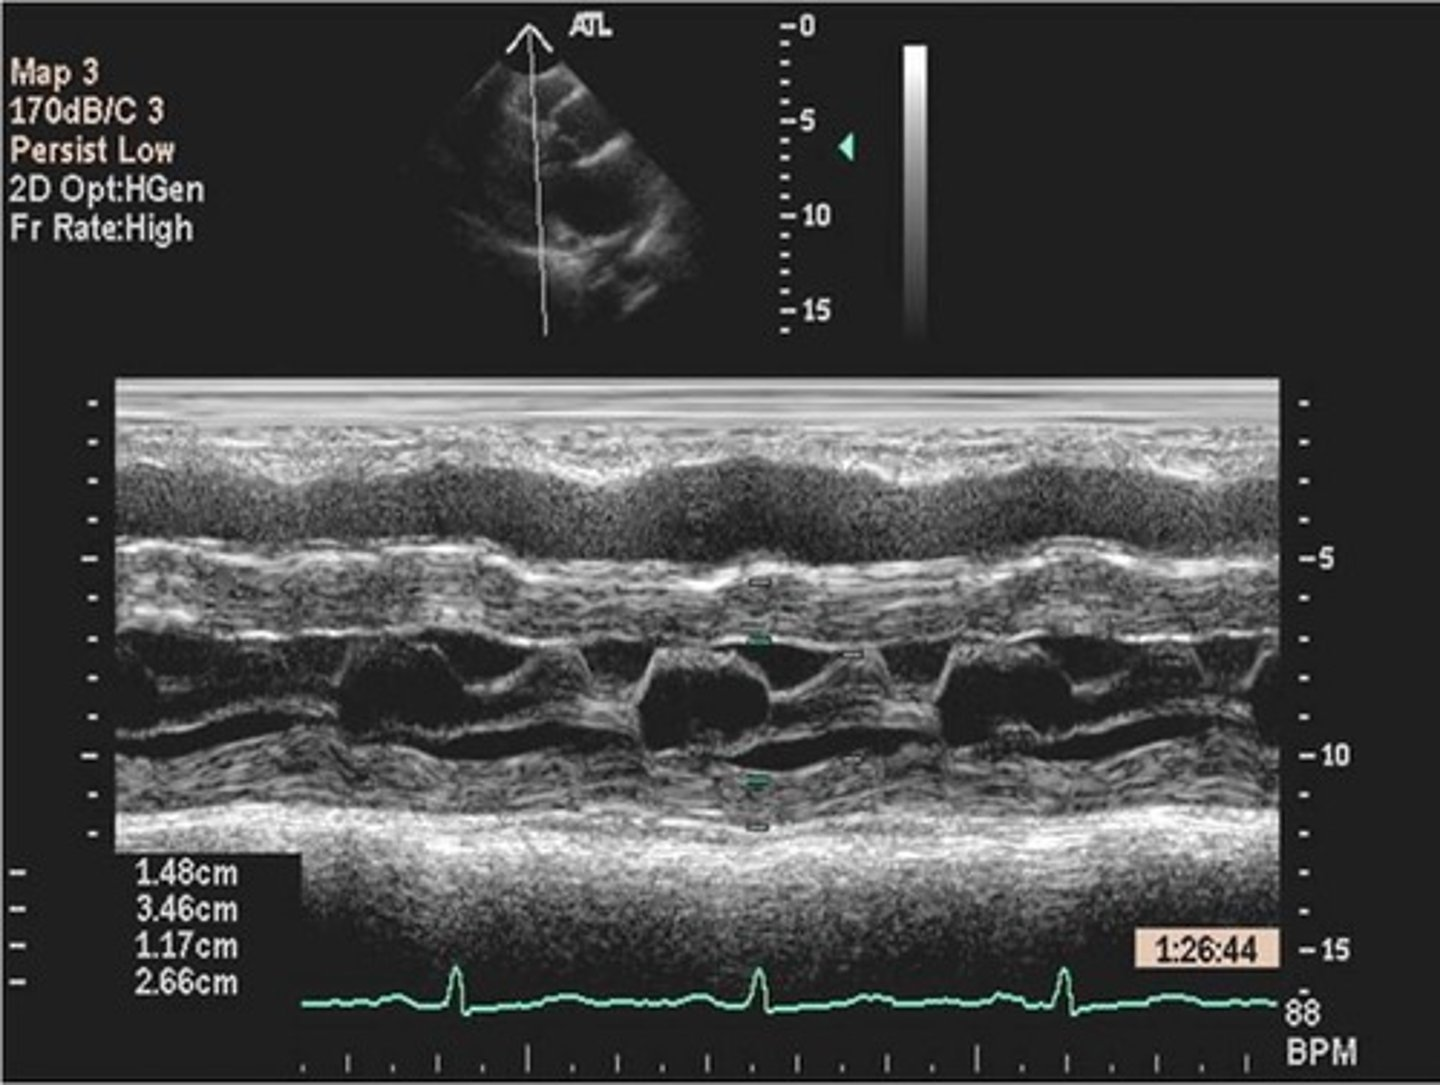

EPSS

distance between E point and IVS (2-7mm)